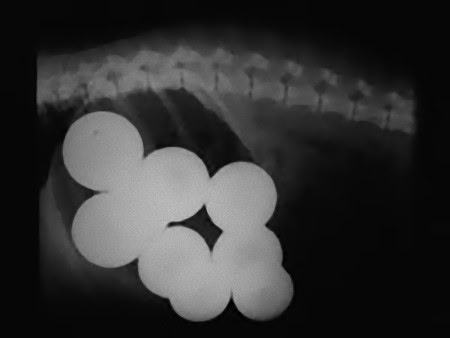

犬が飲み込んだナインボールズ

この画像を大きなサイズで見る